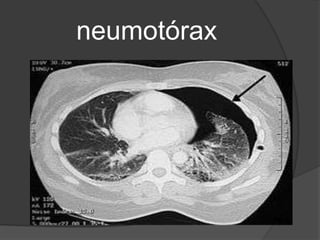

La tomografía computadorizada (TAC) del tórax

tiene valor en el diagnóstico diferencial entre

neumotórax y una bula gigante.